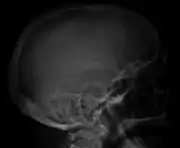

The diagnostic examination of a person with suspected multiple myeloma typically includes a skeletal survey. This is a series of X-rays of the skull, axial skeleton, and proximal long bones. Myeloma activity sometimes appears as "lytic lesions" (with local disappearance of normal bone due to resorption) or as "punched-out lesions" on the skull X-ray ("raindrop skull"). Lesions may also be sclerotic, which is seen as radiodense.[64] Overall, the radiodensity of myeloma is between −30 and 120 Hounsfield units (HU).[65] Magnetic resonance imaging is more sensitive than simple X-rays in the detection of lytic lesions, and may supersede a skeletal survey, especially when vertebral disease is suspected. Occasionally, a CT scan is performed to measure the size of soft-tissue plasmacytomas. Bone scans are typically not of any additional value in the workup of people with myeloma (no new bone formation; lytic lesions not well visualized on bone scan).

Skull X-ray showing multiple lucencies due to multiple myeloma